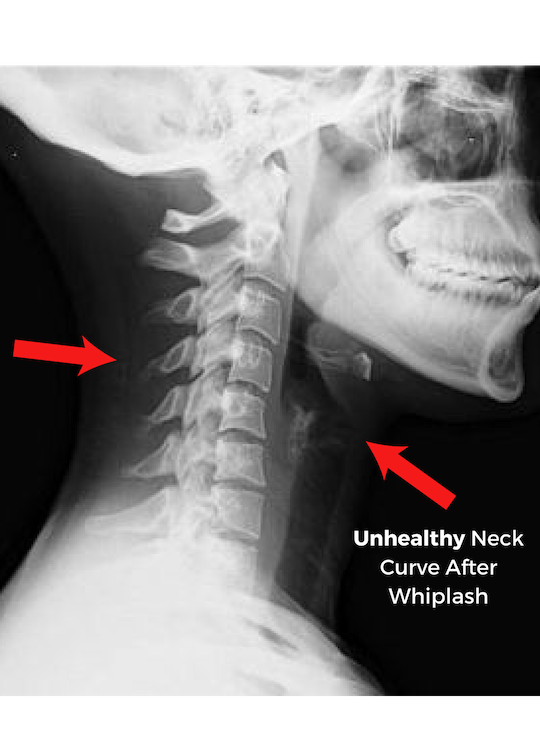

• ​Whiplash is the single greatest threat to auto-accident individuals.

• Untreated whiplash can cause long-term health complications, neck & back strain, nausea, dizziness, severe migraines, & radiating pain across the upper body.